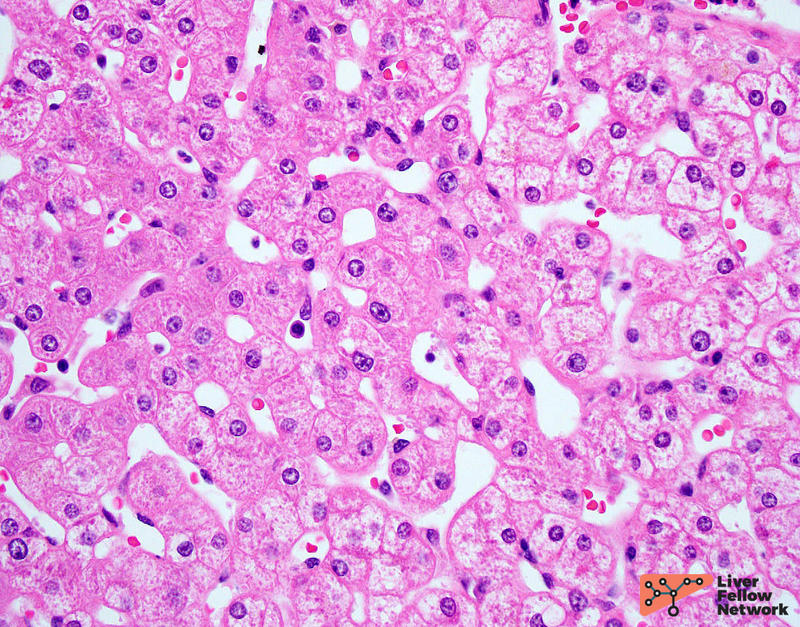

HE/IHC

Histopathology